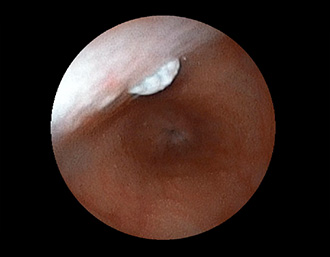

症例3:十二指腸潰瘍(53才男性)

1年前からの慢性胃痛を主訴に当院受診。十二指腸球部前壁に深くて大きな潰瘍(Stage A1)があり、潰瘍底は厚い白苔に覆われ、一部白苔のはみ出しを認める。潰瘍周囲粘膜は浮腫を伴っている。ボノプラザンフマル酸塩投薬で治療開始しました。

(FICE画像)